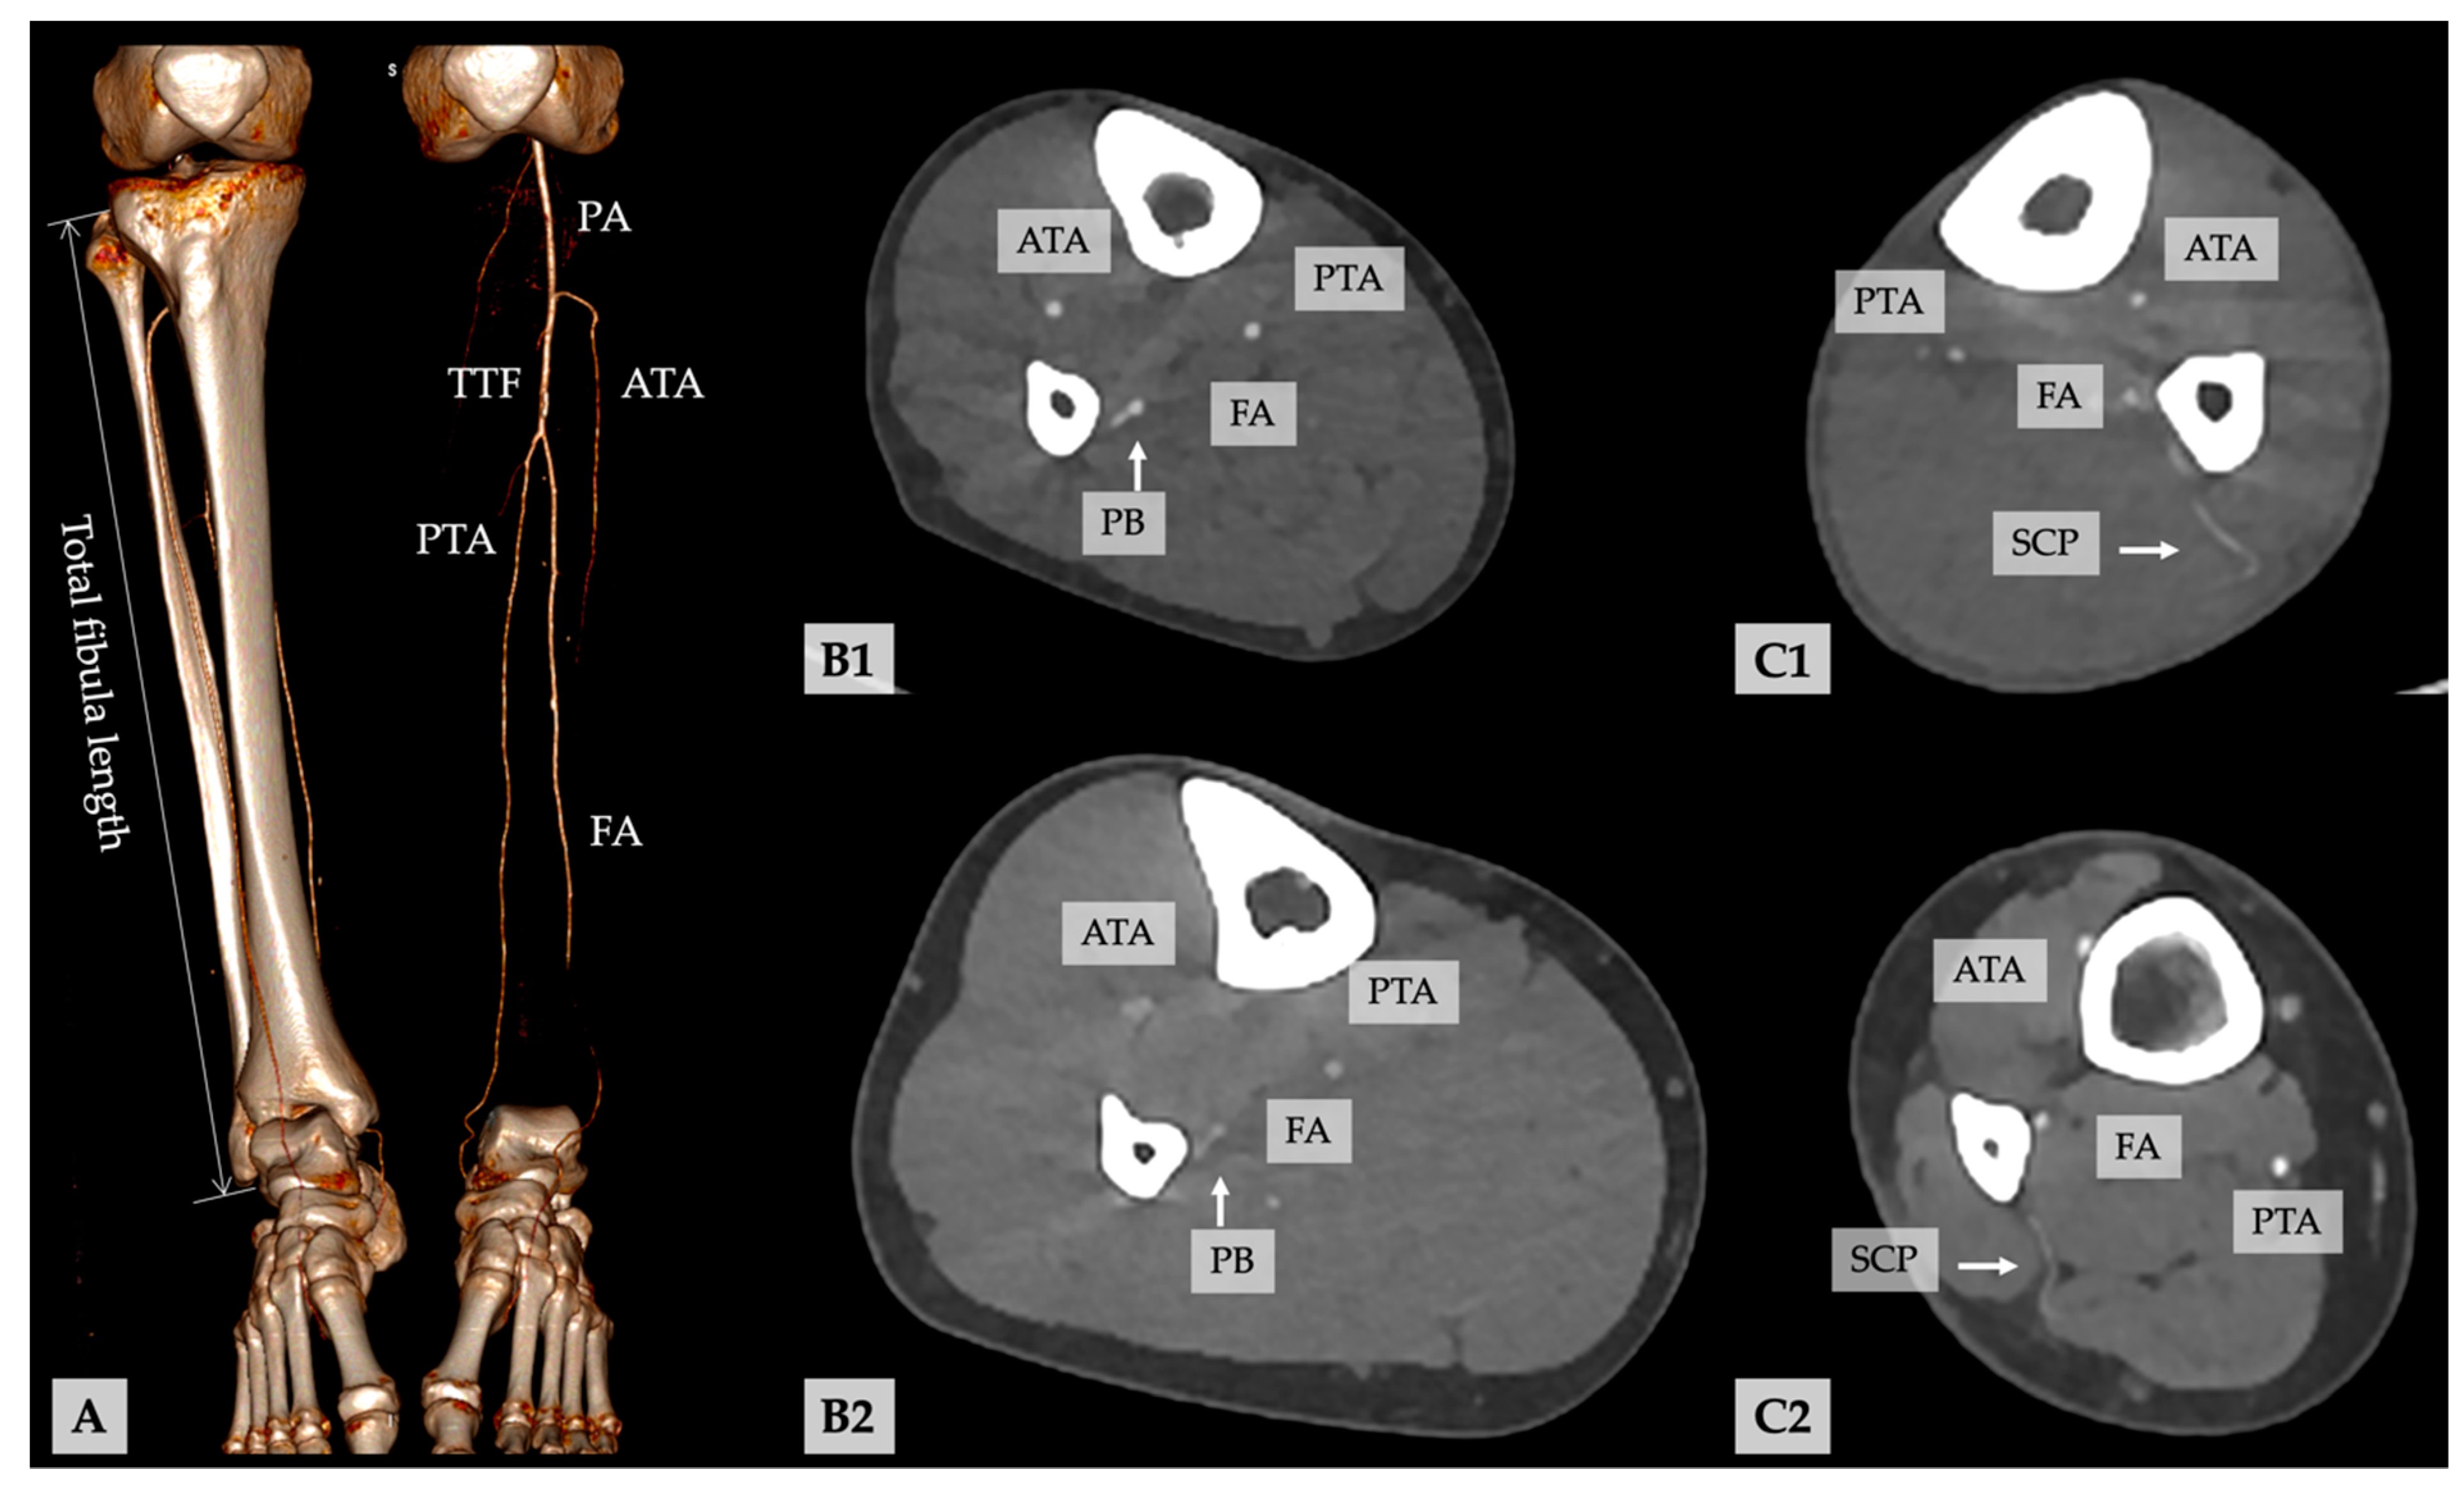

4.2. Is It Possible to Record and to Distinguish Periosteal Branches and Septo-Cutaneous Perforators of the FA, and up to Which Diameter Can These Vessels Be Detected in Routinely Run Preoperative CTA for VSP?

4.3. What Is the Frequency and Distribution of PBs and SCPs of the FA?